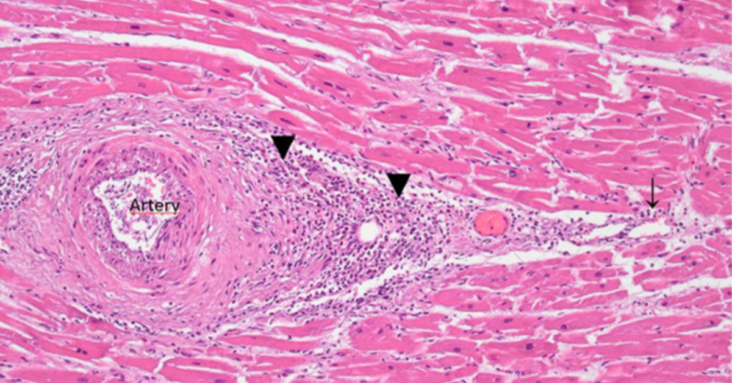

The current report presents the case of a 76-year-old man with Parkinson’s disease (PD) who died three weeks after receiving his third COVID-19 vaccination. The patient was first vaccinated in May 2021 with the ChAdOx1 nCov-19 vector vaccine, followed by two doses of the BNT162b2 mRNA vaccine in July and December 2021. The family of the deceased requested an autopsy due to ambiguous clinical signs before death. PD was confirmed by post-mortem examinations. Furthermore, signs of aspiration pneumonia and systemic arteriosclerosis were evident. However, histopathological analyses of the brain uncovered previously unsuspected findings, including acute vasculitis (predominantly lymphocytic) as well as multifocal necrotizing encephalitis of unknown etiology with pronounced inflammation including glial and lymphocytic reaction. In the heart, signs of chronic cardiomyopathy as well as mild acute lympho-histiocytic myocarditis and vasculitis were present. Although there was no history of COVID-19 for this patient, immunohistochemistry for SARS-CoV-2 antigens (spike and nucleocapsid proteins) was performed. Surprisingly, only spike protein but no nucleocapsid protein could be detected within the foci of inflammation in both the brain and the heart, particularly in the endothelial cells of small blood vessels. Since no nucleocapsid protein could be detected, the presence of spike protein must be ascribed to vaccination rather than to viral infection. The findings corroborate previous reports of encephalitis and myocarditis caused by gene-based COVID-19 vaccines.